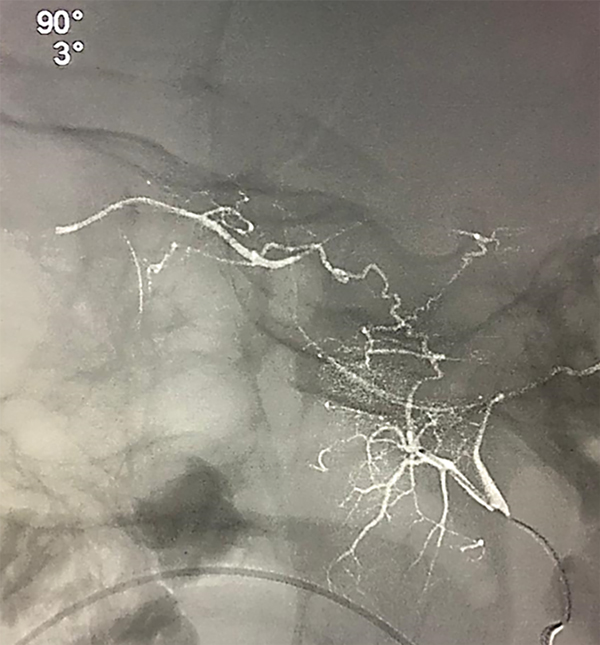

Puede presentarse la situación de observar escaso reflujo hacia la arteria carótida interna durante la adquisición superselectiva, esto no disminuye la efectividad siempre y cuando se logre una correcta opacificación de la coroides y se inyecten las drogas de manera pulsada y suave, según lo descripto por Jabbour et al. Si la maniobra no es satisfactoria se vuelve a repetir este paso. Si luego de dos (hasta tres) maniobras no se consigue cateterizar la arteria oftálmica se asume que no tiene un ostium “favorable” por lo que se da lugar a la siguiente fase de la técnica. Se posiciona el microcatéter en la arteria carótida externa y se cateteriza super-selectivamente la arteria meníngea media (o meníngea accesoria) para visualizar la anastomosis con arteria oftálmica (técnica 2 en 2 completa, fig. 5 y 6).

Fig 5: Cateterización superselectiva de arteria meníngea media (AMM) derecha, se observa anastomosis con arteria oftálmica homolateral y correcta opacificación de la coroides. Técnica “en dos pasos” o técnica “2 en 2 completa”. Vista lateral estricta. Microcatéter Magic 1.5.